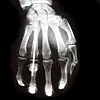

Gravide bør få i seg mer D-vitamin enn resten av befolkningen. Det er vanskelig å få til, særlig her i det høye nord. (Foto: Colourbox)

Vitamin D trengs for å bygge skjelettet, og for å forbygge en rekke andre sykdommer. Gravide trenger ekstra mye av vitaminet, som vi kan få fra sola eller fra kosten.

De skal nemlig ikke bare ta vare på sitt eget skjelett, men også hjelpe til å bygge barnets.